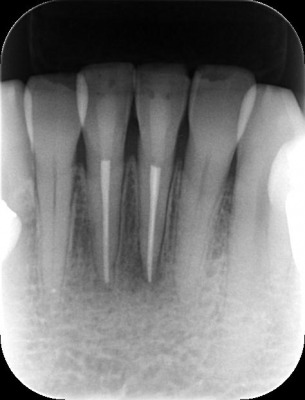

- 処置後約半年

処置前と処置後約半年の比較です。

根尖病巣が治癒していることがよくわかります。